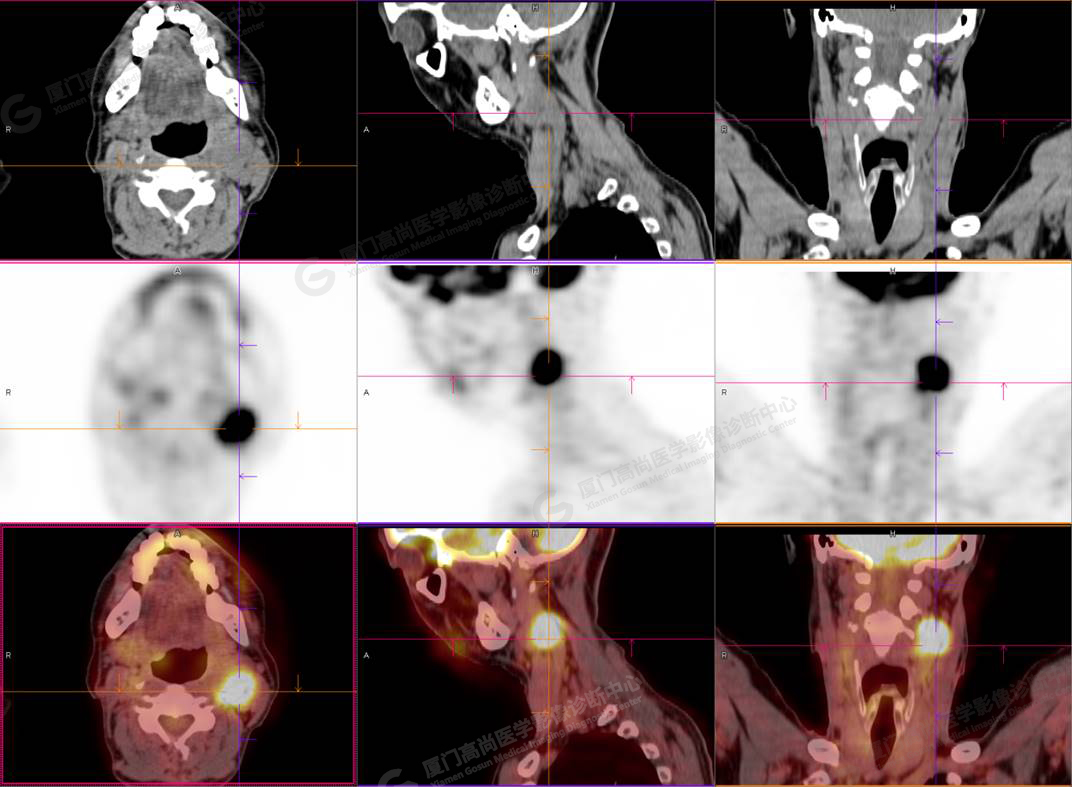

PET/CT影像圖

圖1

PET/CT所見:左側頸部(II區(qū))見腫大淋巴結,大小約2.5cm×2.3cm,其內密度不均,邊界尚清,放射性攝取異常增高,早期SUVmax 11.5,延時SUVmax 14.5。

影像診斷: 左側頸部(II區(qū))腫大淋巴結,代謝異常增高,考慮腫瘤性病變可能性大(淋巴瘤?轉移瘤?),建議病理學檢查明確。